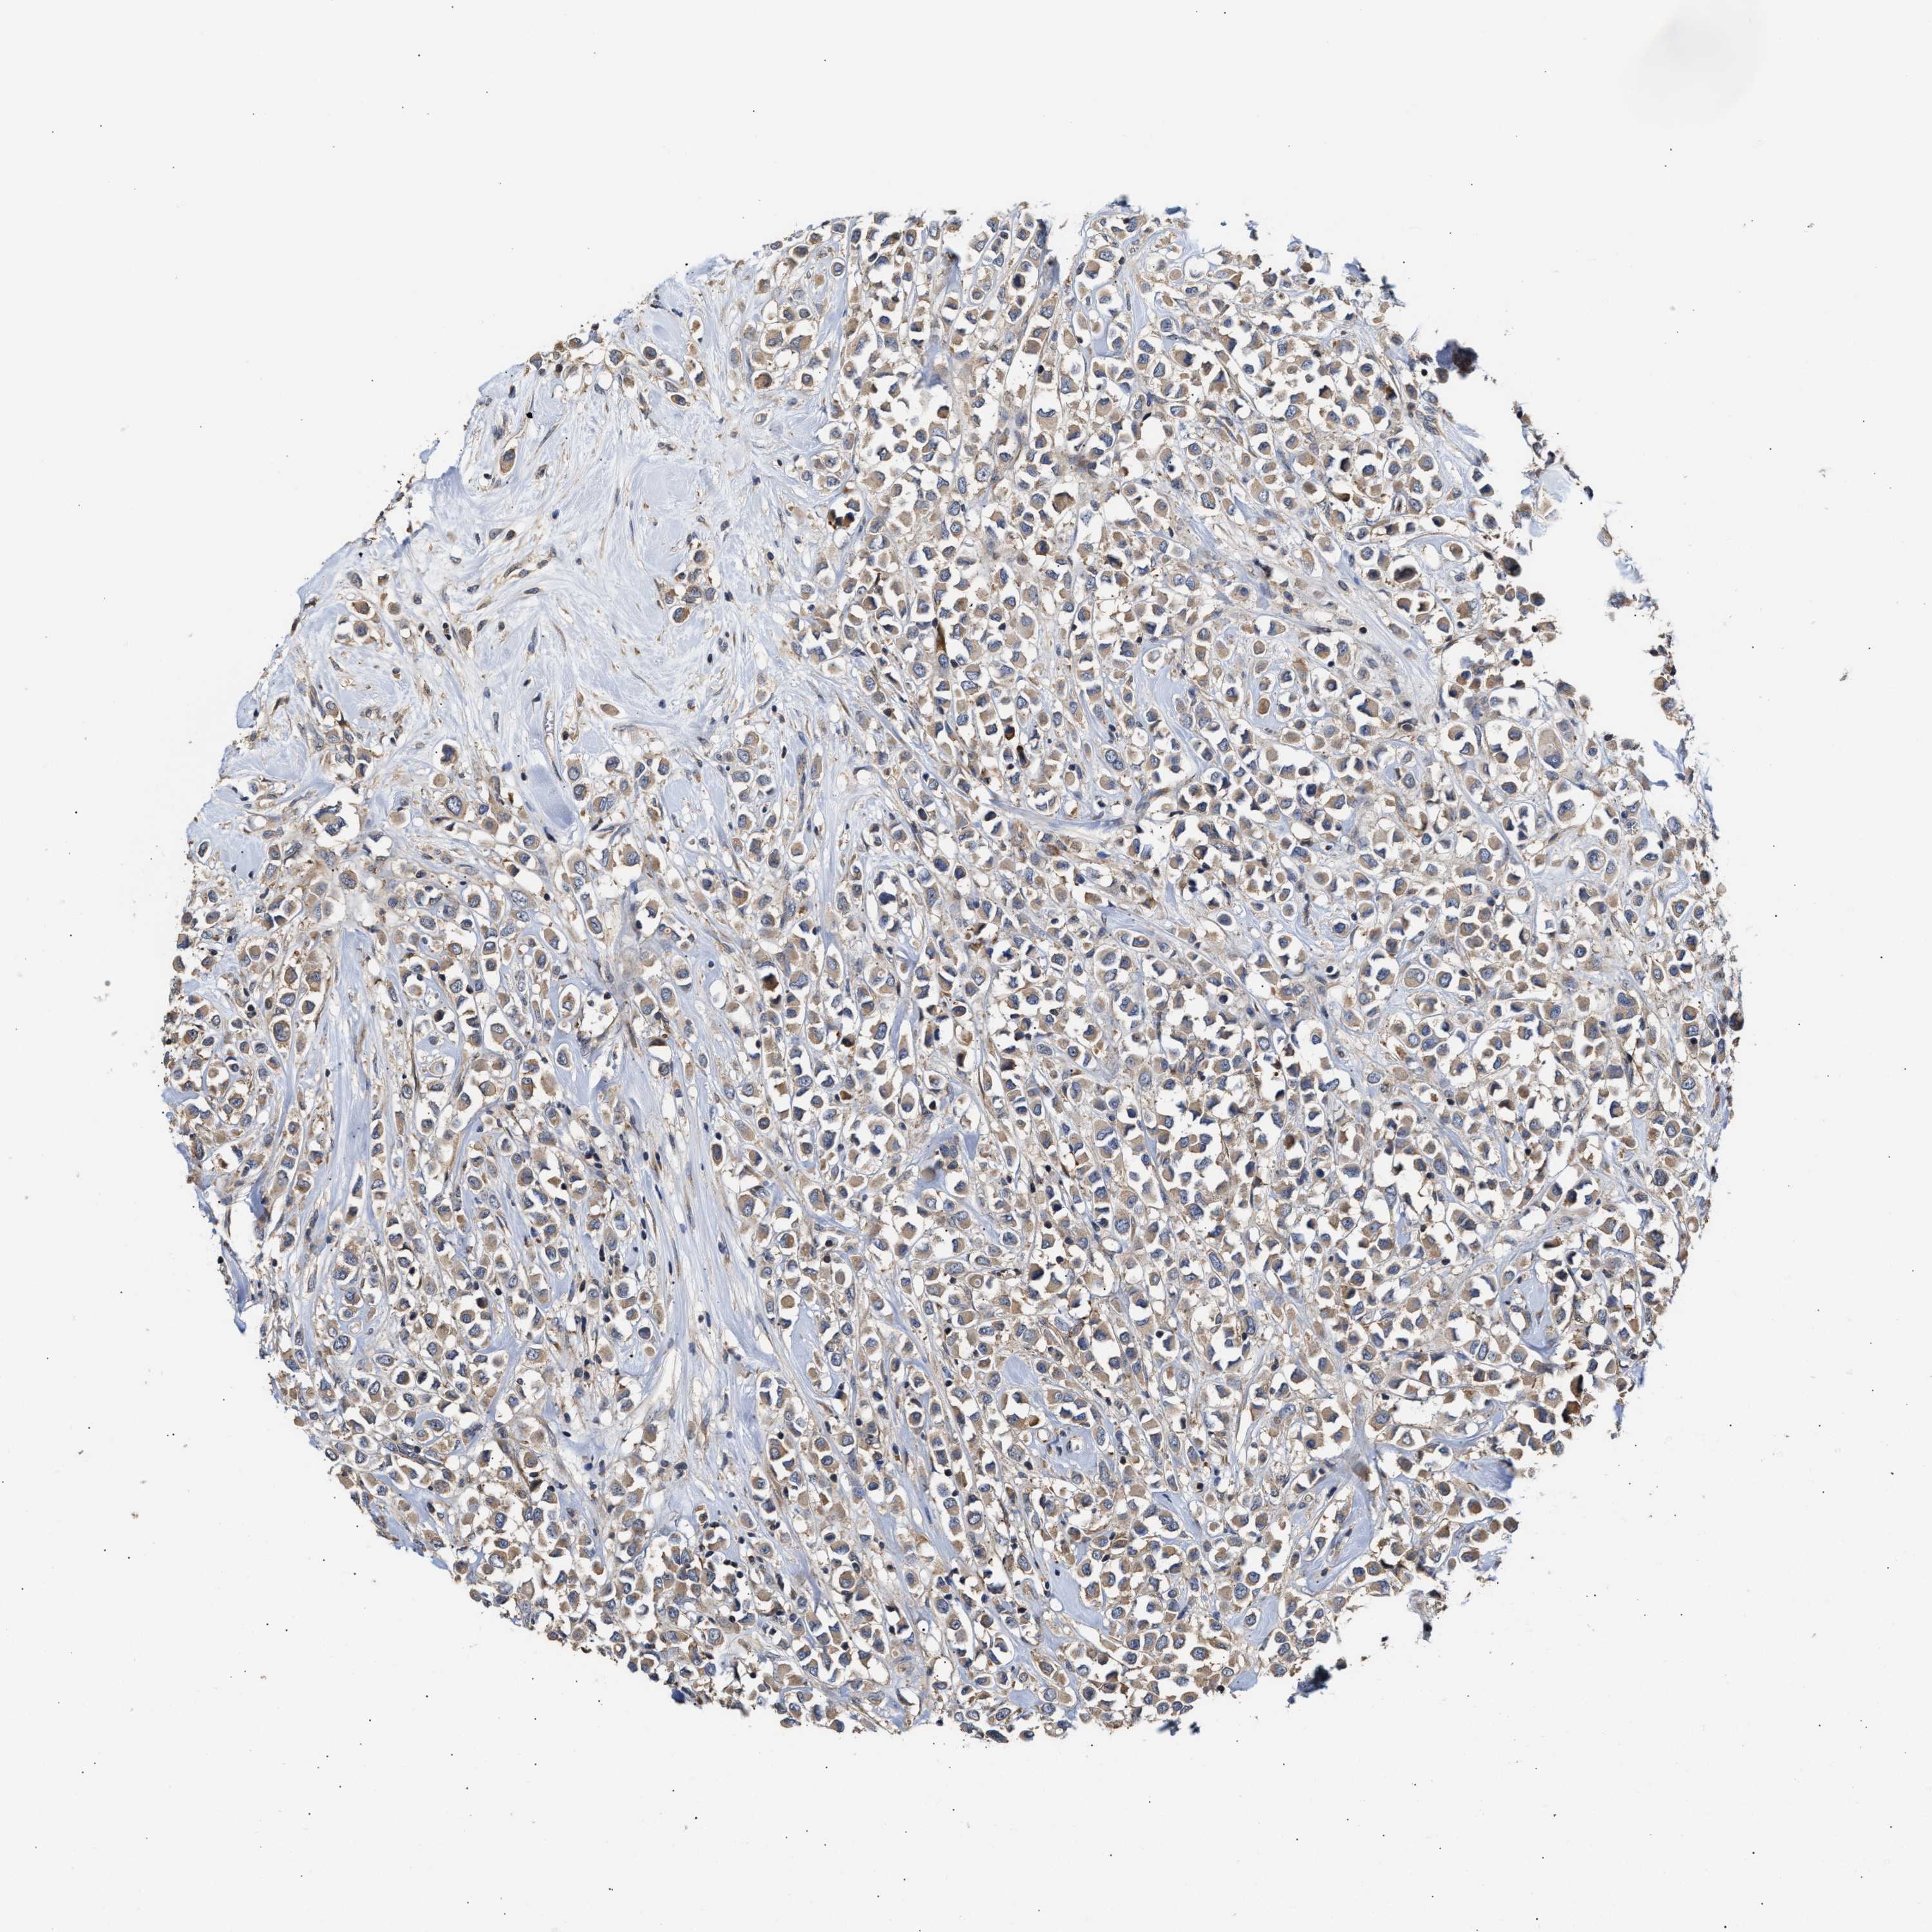

CANCER BREAST CANCER Show tissue menu

BRCA TCGA BRCA VALIDATION PROTEIN EXPRESSION